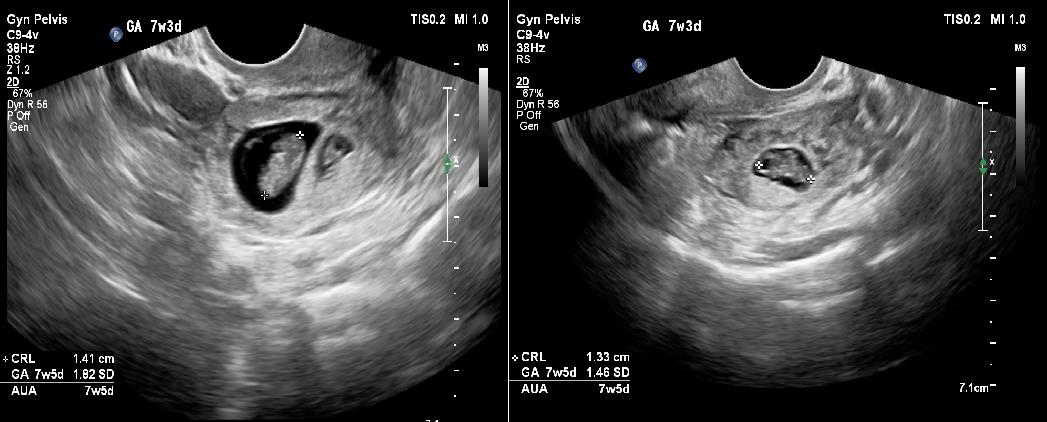

Transabdominal ultrasound revealed a bulky uterus with a thickened endometrium; however, no intrauterine gestational sac was appreciable. A thick-walled cystic structure was noted in the left adnexa with only one fetal pole initially visualized. [Figure 1a and 1b]. Subsequently performed transvaginal ultrasound revealed two gestational sacs in the left adnexa. Twin peak sign was identified, which confirmed dichorionicity. Each gestational sac contained a fetal pole-yolk sac complex [Figure 2a]. Cardiac activity was present in both embryos, confirmed on color Doppler study [Figure 2b]. Crown rump lengths of twin 1 and twin 2 were 13.3 mm and 14.1 mm, respectively, both corresponding to a gestational age of 7.5 weeks each. [Figure 3a and 3b].

Figure 2: a)-Two gestational sacs with twin peak sign, each having its own

fetal pole-yolk sac complex, suggesting a dichorionic diamniotic pregnancy

b)-Presence of cardiac activity in both foetal poles was confirmed on colour

Doppler study.